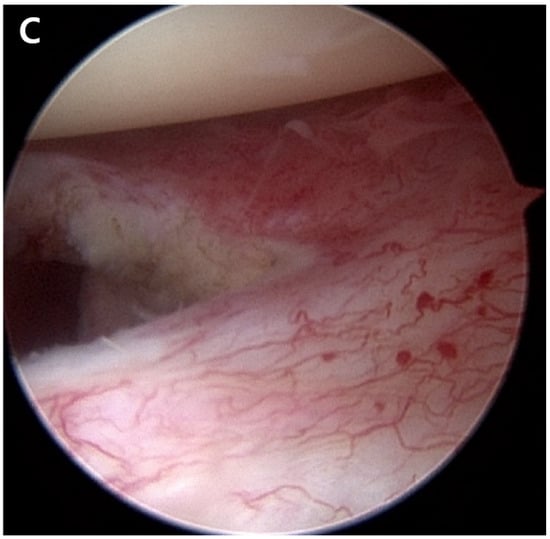

At 15 months post-operation, the patient developed recurring right shoulder pain. Subsequently, he sought treatment at another orthopedic hospital. He received two triamcinolone intra-articular injections and underwent four prolotherapy injections using a mixture of saline, dextrose, and lidocaine over a six-month period from 15 to 21 months post-operation. The patient returned to the hospital 21 months after the ACR with right shoulder pain. Plain shoulder anteroposterior radiography and MRI showed a subchondral cyst and a high bone marrow signal on the epiphysis of the superomedial area of the humeral head on T2-weighted images, suggesting avascular osteonecrosis at Cruess stage II (Figure 4). The patient denied any traumatic injury, radiotherapy, exacerbation of chronic hepatitis, alcohol consumption, or use of other medications. At 3 years post-operation, his VAS score was 3, his ASES score was 63, and his CMS score was 59, indicating increased discomfort. As the patient found the discomfort tolerable in terms of both work capacity and activities in daily life, we decided to maintain the current status and continue observation until osteonecrosis progressed (Figure 5).

Figure 4.

(A). Postoperative plain radiograph obtained 21 months post-ACR. (B). Oblique coronal T1 fat-suppressed MRI. (C). Oblique coronal T2 fat-suppressed MRI shows osteolytic changes in the superomedial humeral head. MRI shows cystic changes in the epiphyseal area, but articular congruity remains preserved.